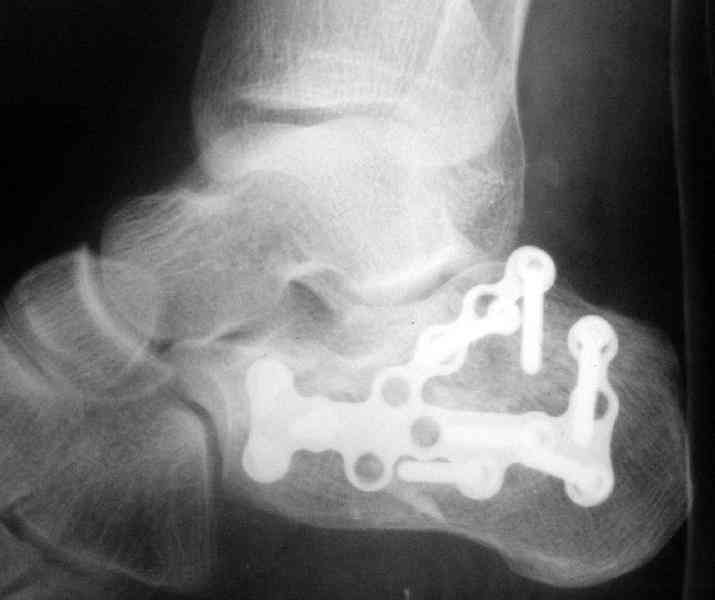

Re: Перелом пяточной кости

Пяточной пластиной

Открытый и закрытый способы лечения.